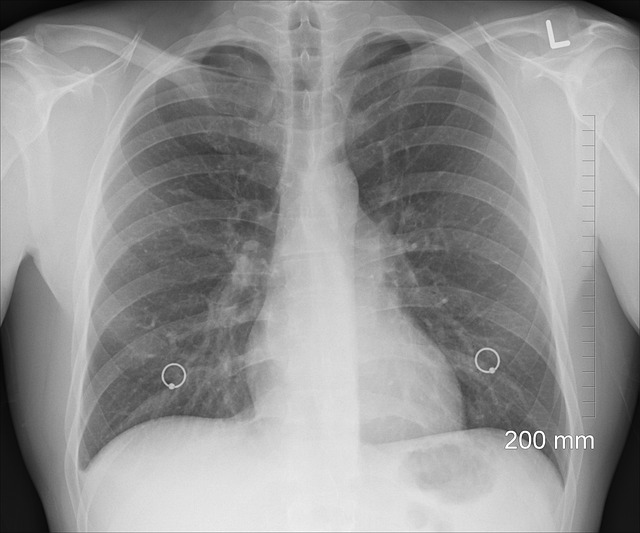

X-레이는 전자기 스펙트럼의 일부로, 물체를 투과할 때 다른 밀도를 가진 조직에 따라 다르게 흡수됩니다. 이 차이를 이용해 뼈와 연조직 등 인체 내부 구조의 이미지를 생성합니다. X-레이는 골절이나 폐 질환 같은 상태를 진단하는 데 특히 유용합니다.